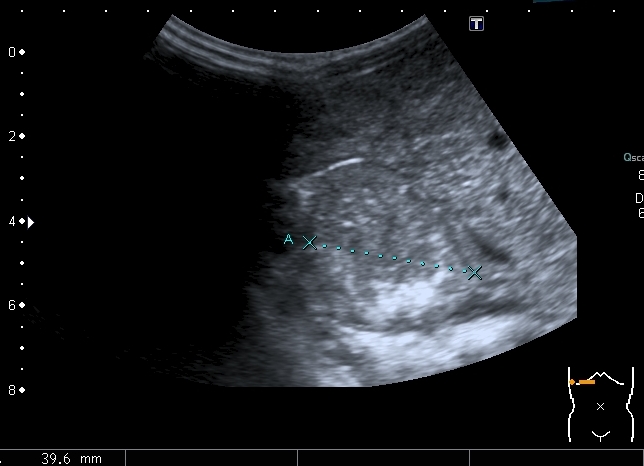

При УЗИ: печень резко увеличена, больше за счёт левой доли

Правая доля

Паренхима печени -гиперэхогенная , неоднородная, практически полностью замещена нодулярными образованиями, некоторые из них с "гало" и кальцификацией